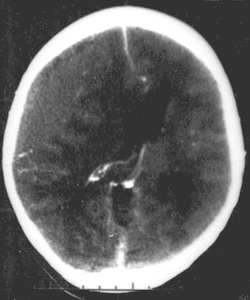

CT scan showing epidural hematoma, a type of traumatic brain injury (upper left)

Brain trauma in the developing human is a common cause (over 400,000 injuries per year in the US alone, without clear information as to how many produce developmental sequellae)[63] of neurodevelopmental syndromes. It may be subdivided into two major categories, congenital injury (including injury resulting from otherwise uncomplicated premature birth)[64] and injury occurring in infancy or childhood. Common causes of congenital injury are asphyxia (obstruction of the trachea), hypoxia (lack of oxygen to the brain), and the mechanical trauma of the birth process itself.[65]